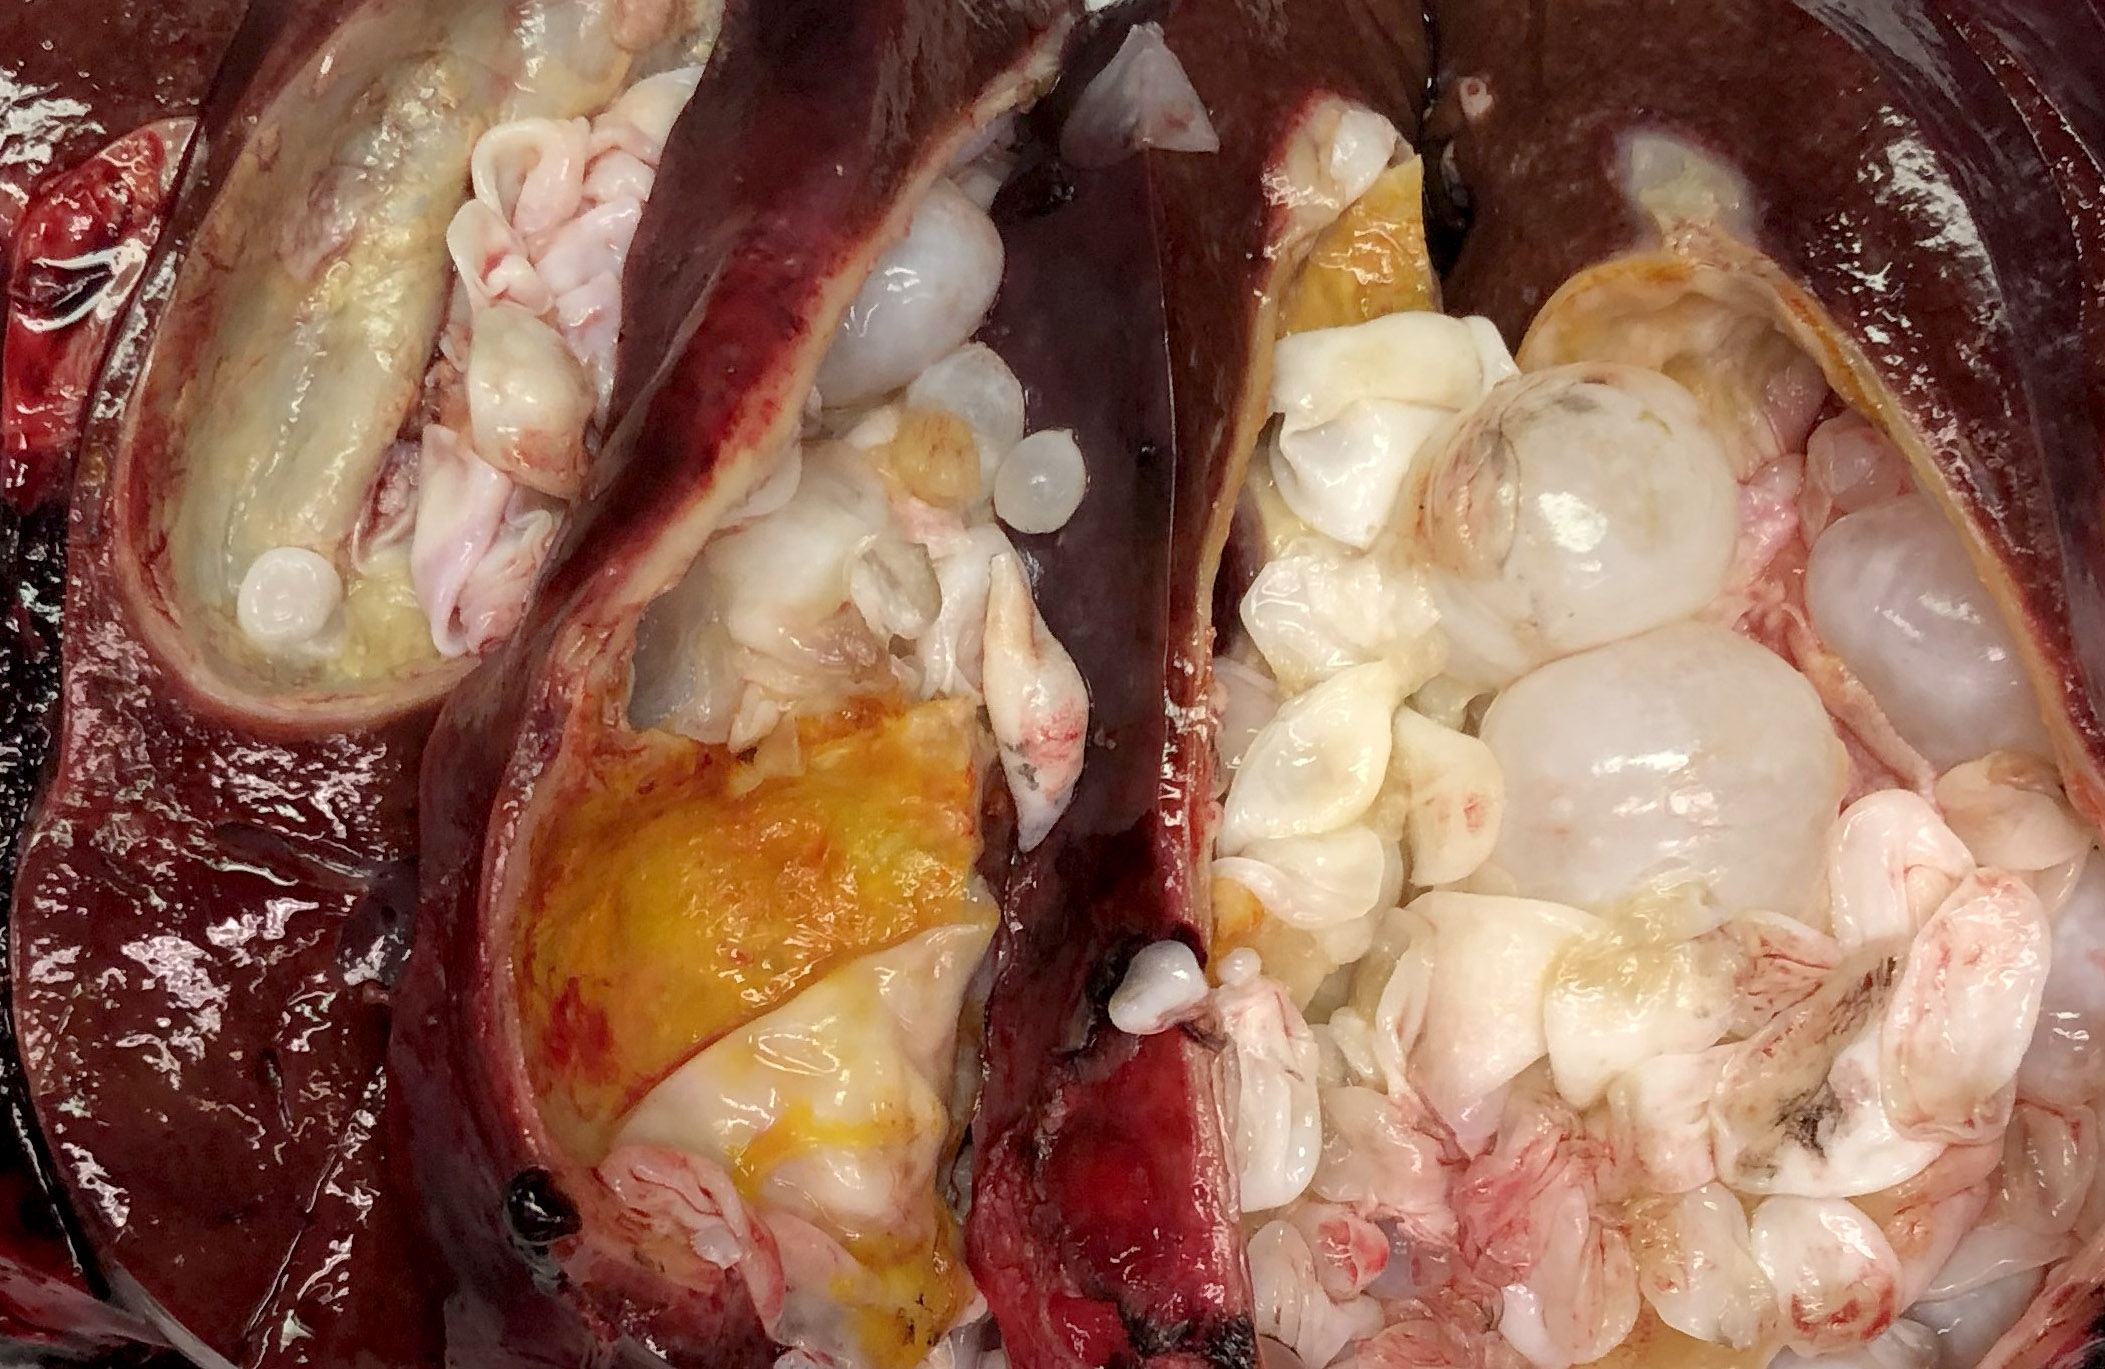

- Echinococcus granulosus: typical cyst is spherical, up to 30 cm or more in diameter, has a fibrous rim and frequently contains several daughter cysts

- Echinococcus multilocularis: multilocular, necrotic, cystic cavities containing thick pasty material; fibrous rim is absent

Gross images